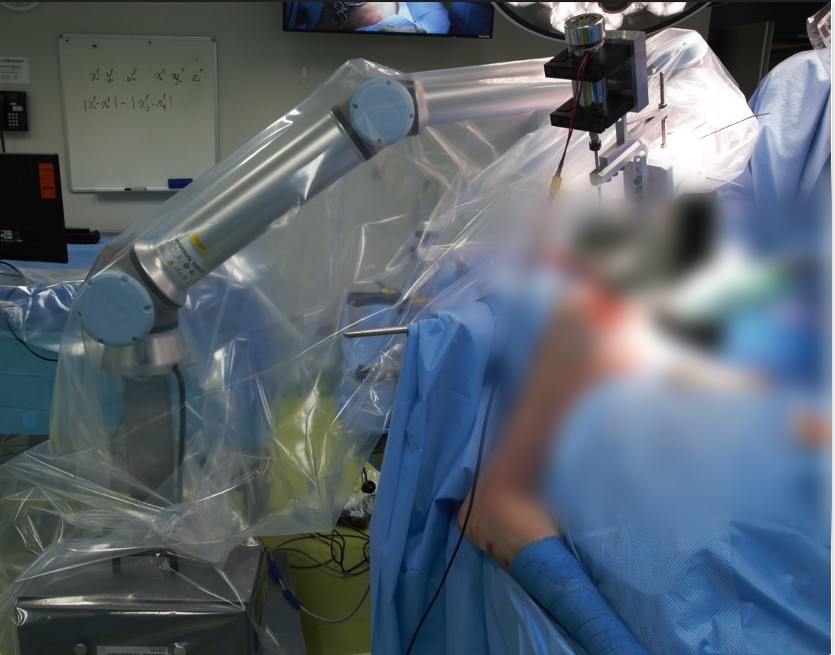

Phantom demonstration of robotic-assisted surgical system for total hip replacement

- Li, T., Walker, P., Khonasty, R., van de Graaf, V.A., Yelf, E., Zhao, L. and Huang, S., 2024. Robotic‐assisted burring in total hip replacement: A new surgical technique to optimise acetabular preparation. The International Journal of Medical Robotics and Computer Assisted Surgery, 20(1), p.e2615.

- Walker, P., Li, T*, Khonasty, R., Ponnanna, K.M., Kuo, A., Zhao, L. and Huang, S., 2022. Proof of concept study for using UR10 robot to help total hip replacement. The International Journal of Medical Robotics and Computer Assisted Surgery, 18(2), p.e2359.

Cadaver Experiment of Robotic Burring System for Total Hip Replacement Surgery.